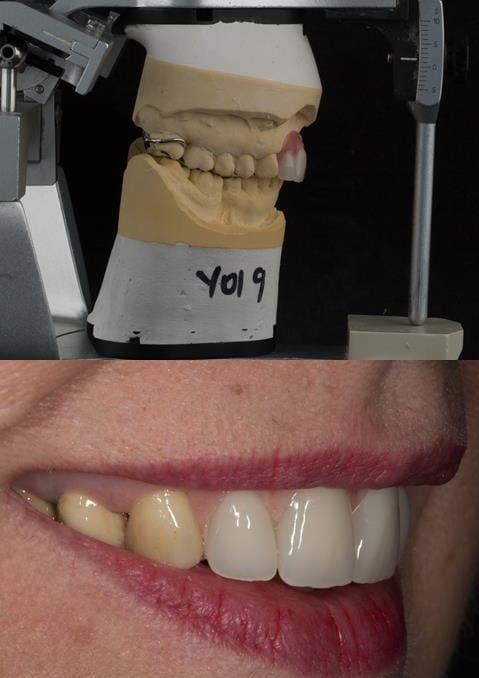

Provision of a maxillary cobalt chromium based partial denture/protective occlusal splint in a heavily restored dentition

- Extract the upper 2-2 teeth and replace with an interim acrylic based partial denture. Reline the interim denture over 9 - 12 months, replacing with a definitive cobalt chromium based partial denture. The definitive denture would ideally be designed as an occlusal protective splint to reduce the the potential for mechanical wear and breakages of the moderately/heavily restored maxillary dentition. In addition, should further upper teeth require extraction they could be added on to the denture cobalt chromium framework - therefore a new prosthesis would not be required as future teeth are lost. This option would produce an excellent aesthetic outcome. This is the option the patient chose to have.

Following consultation and second discussion appointment the patient chose to have option 3 namely, a maxillary cobalt chromium based partial denture/protective occlusal splint. The clinical situation and treatment process is shown in detail below with photographs. The patient was successfully rehabilitated with this and her quality of life considerably improved. The clinical work was provided by Finlay and the technical work by Rowan.